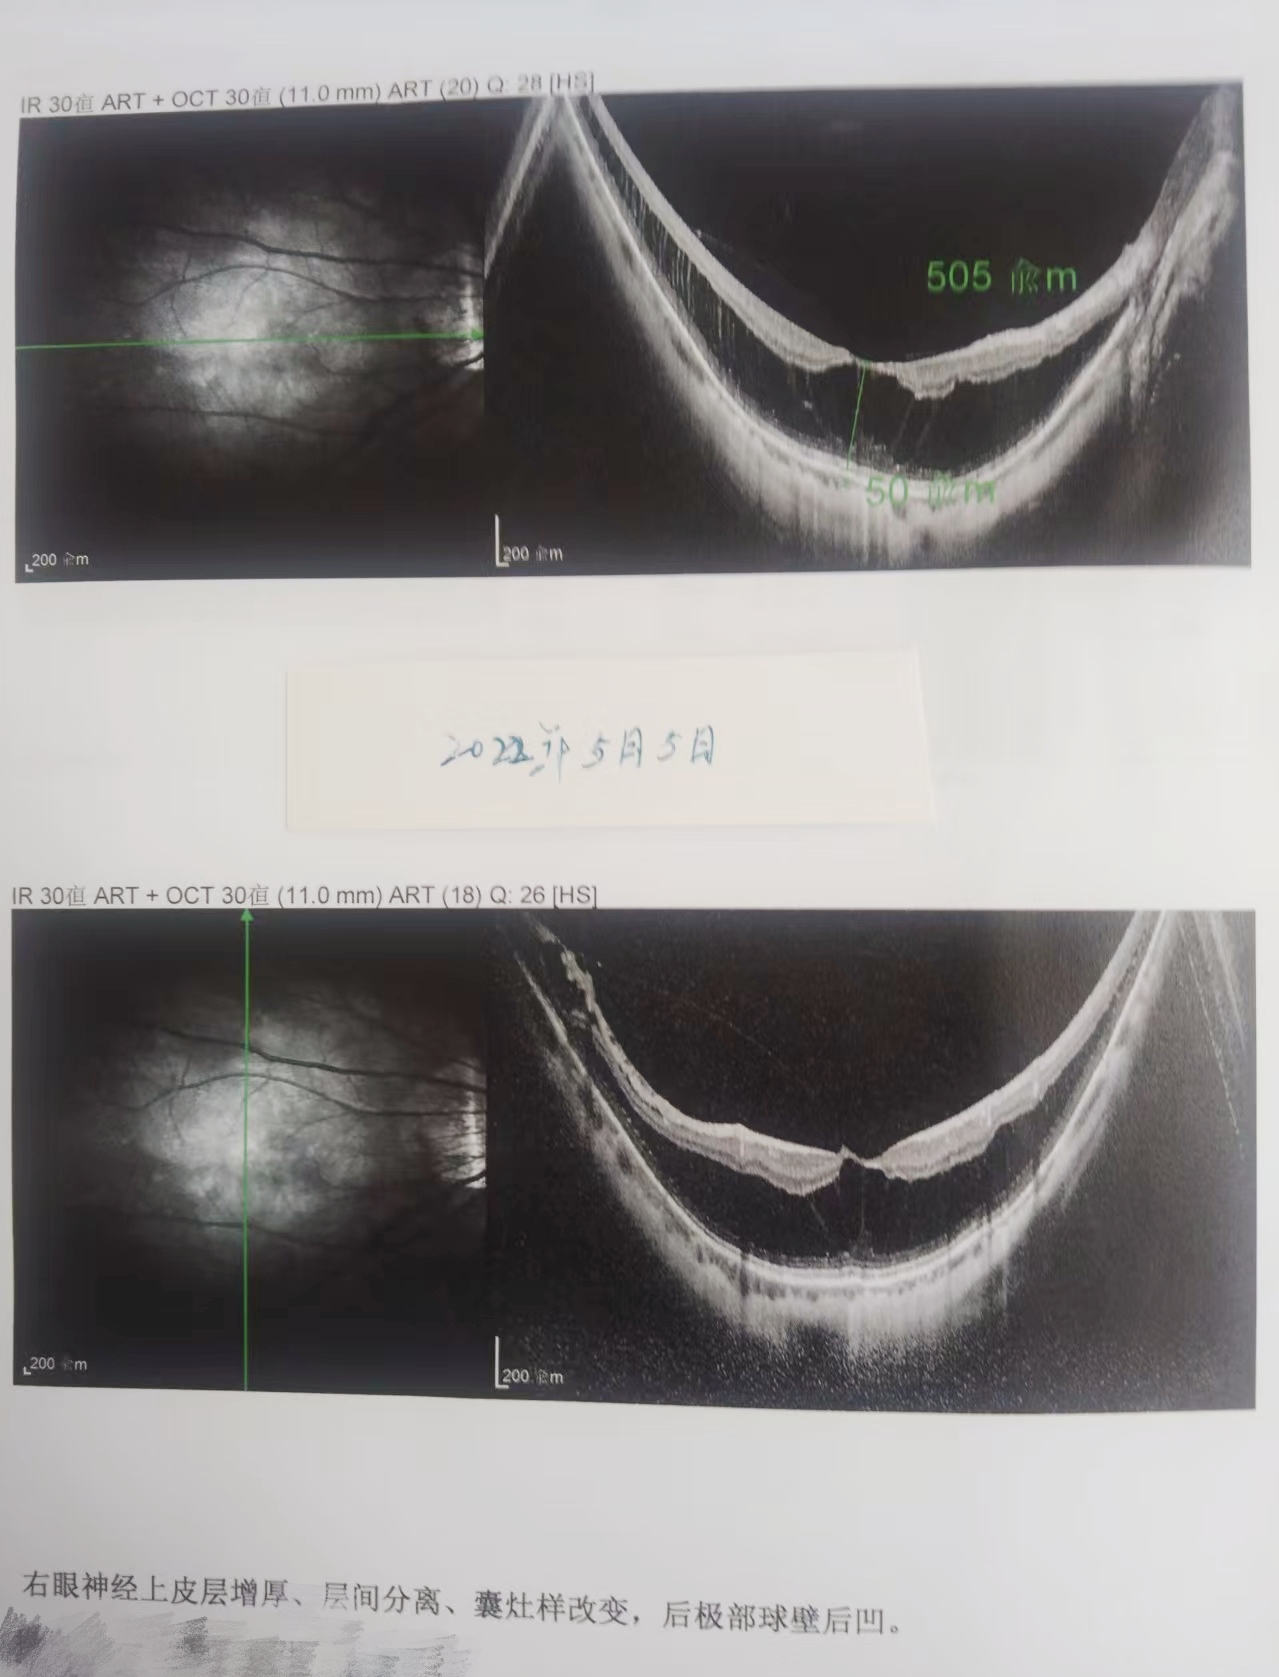

家住泉州的林女士(化名),年近60岁,因右眼近视超1000度,2022年5月因视力骤降,视物变形确诊为右眼黄斑劈裂(下图1)。

(图1 检查报告)

2022年5月在外院进行右眼黄斑劈裂手术;2025年11月因“右眼闪光感增强且眼前有黑影遮挡”被确诊为“右眼黄斑(区)多发裂孔性视网膜脱离”(下图2)。